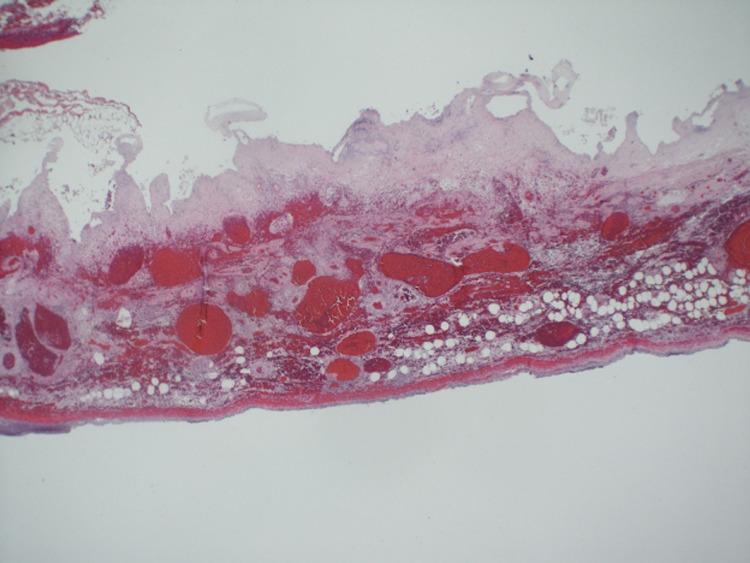

Gallbladder volvulus is a rarely reported and diagnosed condition. We present a case of an elderly female with right lower quadrant pain mimicking acute appendicitis without conclusive imaging; however, due to worsening serological laboratory findings and sepsis picture, an exploratory laparotomy was performed. A necrotic gallbladder was removed, diagnosing gallbladder volvulus. A systemic literature review showed the difficulty in making a diagnosis and the uniqueness of our patient presentation. A high level of clinical suspicion for gallbladder volvulus must be maintained and should be included in the differential diagnosis in elderly women with an acute abdomen, as complications can be severe.